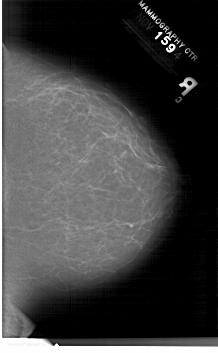

A_1202_1.LEFT_MLO

LEFT_MLO LINES 6511 PIXELS_PER_LINE 4471 BITS_PER_PIXEL 12 RESOLUTION 43.5 OVERLAY

FILE: A_1202_1.LEFT_MLO.OVERLAY

TOTAL_ABNORMALITIES 1

ABNORMALITY 1

LESION_TYPE CALCIFICATION TYPE PLEOMORPHIC DISTRIBUTION SEGMENTAL

ASSESSMENT 5

SUBTLETY 3

PATHOLOGY MALIGNANT

TOTAL_OUTLINES 1

BOUNDARY